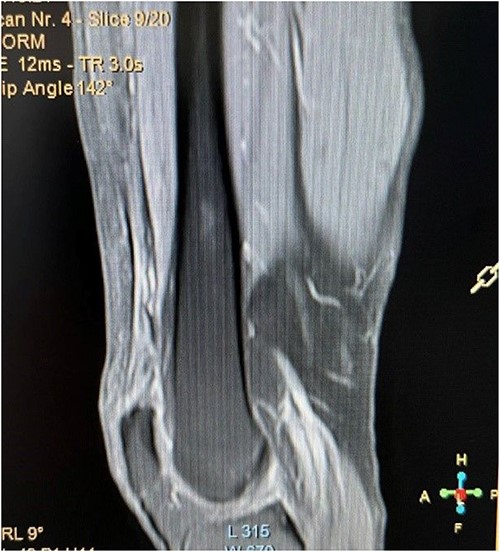

A 62-year-old male presented to emergency department of our hospital with complaints of low back pain and decrease range of motion of the right knee due to a fall from standing height. The patient was unable to weight bear and to perform a straight leg raise. His past medical history revealed no significant records. Clinical examination revealed a low back pain without neurological deficit and tenderness at right knee with a palpable defect proximal to the superior pole of the patella. Passive flexion of injured knee was measured as 110° and passive extension was full. Routine laboratory tests including white blood cells (WBC) count, erythrocyte sedimentation rate (ESR), c-reactive protein (CRP), liver and renal function were within normal ranges. The X-rays of the knee were normal without findings of patella baja and osseous pathology (Fig. 1), but the X-rays of the pelvis revealed bilateral sacroiliac arthritis. Based on this finding, further laboratory evaluation revealed a positive HLA-B27. An ultrasound scan performed externally showed a hypoechoic gap and quadriceps complete tear was noted. Magnetic resonance imaging (MRI) confirmed the findings seen on ultrasound with the difference that the rectus femoris (RF) was intact and there was a rupture of intermedius tendon (IT) combined with a partial rupture of vastus medialis. MRI sequences, especially T2W images revealed an intramuscular hematoma and discontinuity in the vastus IT (Figs 2 and 3). A small fluid filled defect, in the vastus intermedius just proximal to the insertion of quadriceps into the patella was also detected. The rectus femoris and vastus lateralis (VL) were intact. The defect in vastus intermedius measured ⁓5 cm from its patellar insertion.

Fat saturated proton density sagittal view showing the rupture of the vastus IT with an intact rectus femoris tendon.